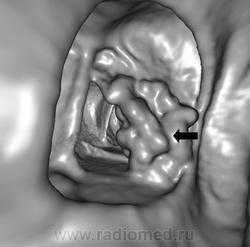

Картина нормального пищевода при эндоскопическом ультразвуковом исследовании.

Стенка пищевода не утолщена, контуры ровные, параэзофагеальная клетчатка не изменена, увеличенные регионарные лимфатические узлы не визуализируются. Картина нормального пищевода при компьютерной томографии.

На всем протяжении стенка пищевода не утолщена, регионарные лимфатические узлы не визуализируются:

а — верхняя треть пищевода; б — средняя треть пищевода;

в — нижняя треть пищевода; г — сагиттальная реконструкция Картина нормального пищевода при рентгенологическом исследовании при тугом наполнении и двойном контрастировании: